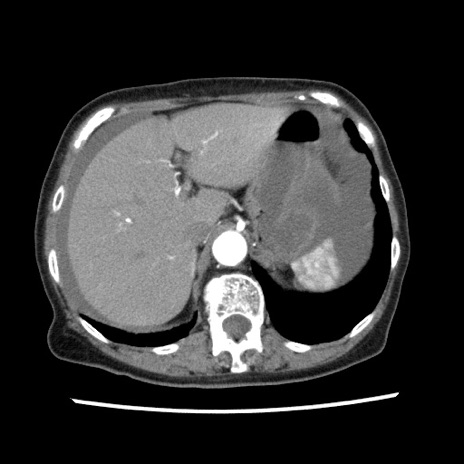

【症例】80歳代女性

【主訴】腹痛

【現病歴】8時間前から腹痛あり来院。

【既往歴】糖尿病、脂質異常症、子宮体癌にて子宮全摘術

【身体所見】意識清明・会話良好だが腹痛で苦悶様、全腹部にわたって反跳痛と圧痛あり

【データ】WBC 13600、CRP 0.14、LDH 224、CK 90